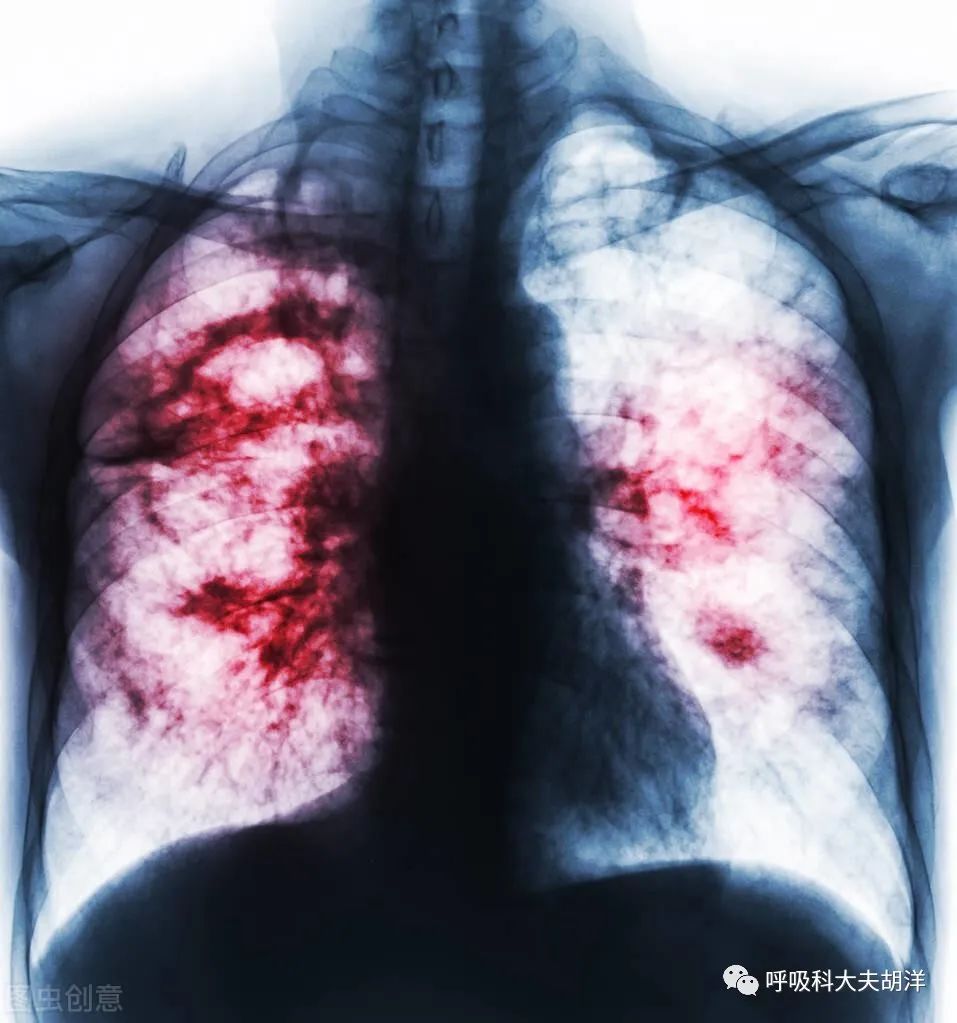

为何明明是肺癌,却表现出肺炎的征象呢?有一种肺癌叫肺炎型肺癌!肺炎型肺癌在胸部CT上表现为斑片状或大片状模糊阴影的肺癌,临床表现有咳嗽、咳痰、发热、胸闷、胸痛等等症状,这种呼吸道症状缺乏特异性,与其他肺部疾病差不多,而且在影像学上肺炎型肺癌与“肺炎”也极其相似,很容易被误诊为肺炎、肺结核、支气管扩张合并感染、间质性肺炎等疾病,进而延误治疗。所以,抗炎治疗后复查非常关键。

肺炎型肺癌是周围型肺癌的一种特殊表现形式,其病理基础可能是源于细支气管或肺泡的癌组织本身呈浸润性发展,在气道内播散时,癌细胞被覆于肺泡壁表面,并沿肺泡壁作贴壁状生长,特别是早中期癌灶,在未形成肺叶或肺段支气管阻塞之前,在CT上呈现出肺炎样大片或斑片状阴影。(此处已添加医疗卡片,请到今日头条客户端查看)